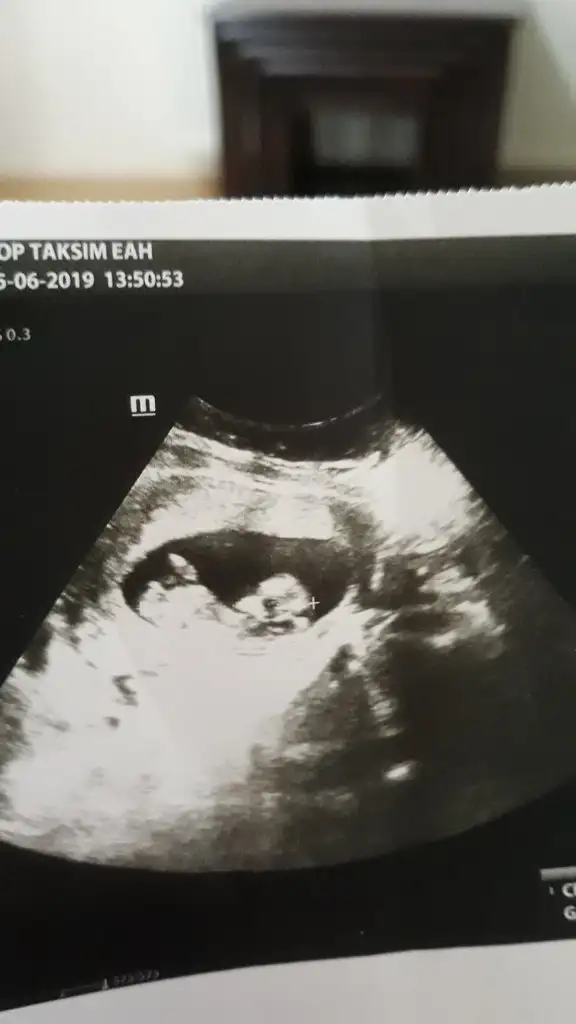

merhaba.. az önce ağrı ile birlikte kanama oldum.. doktora gittim..

usg bakıldı apdominal.. kalbi atıyor ama düşük tehlikesi varmış.. inşallah sağlıklıdır.. 😞

7+3